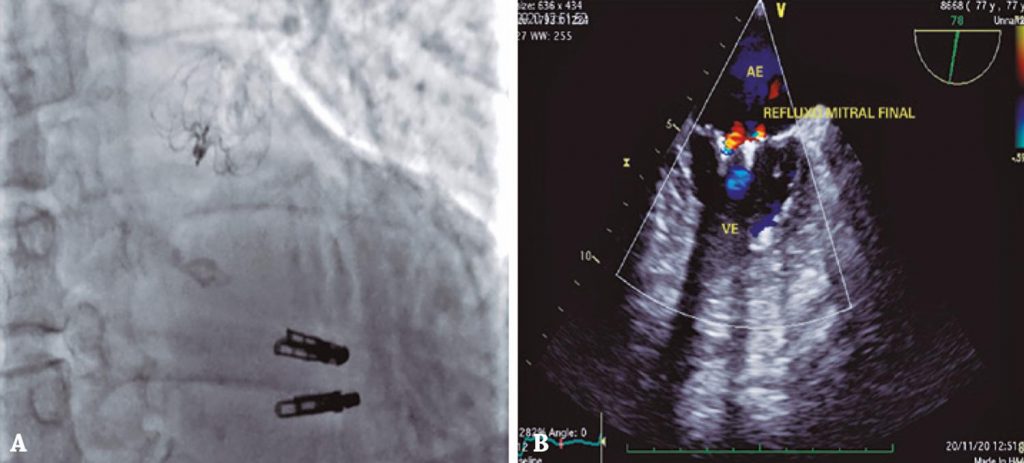

Implante combinado de MitraClip® e oclusão do apêndice atrial esquerdo usando o dispositivo Watchman™

Apresentamos, a seguir, um implante combinado utilizando o sistema MitraClip® e o dispositivo Watchman™ para o tratamento de IM primária e oclusão do AAE. Paciente do sexo feminino, 77 anos, antecedentes de neoplasia de mama tratada com cirurgia e radioterapia, tromboembolismo prévio, fibrilação atrial permanente em uso de ACO (edoxabana), IM importante por degeneração mixomatosa e angiodisplasia de cólon com vários episódios de sangramento intestinal.